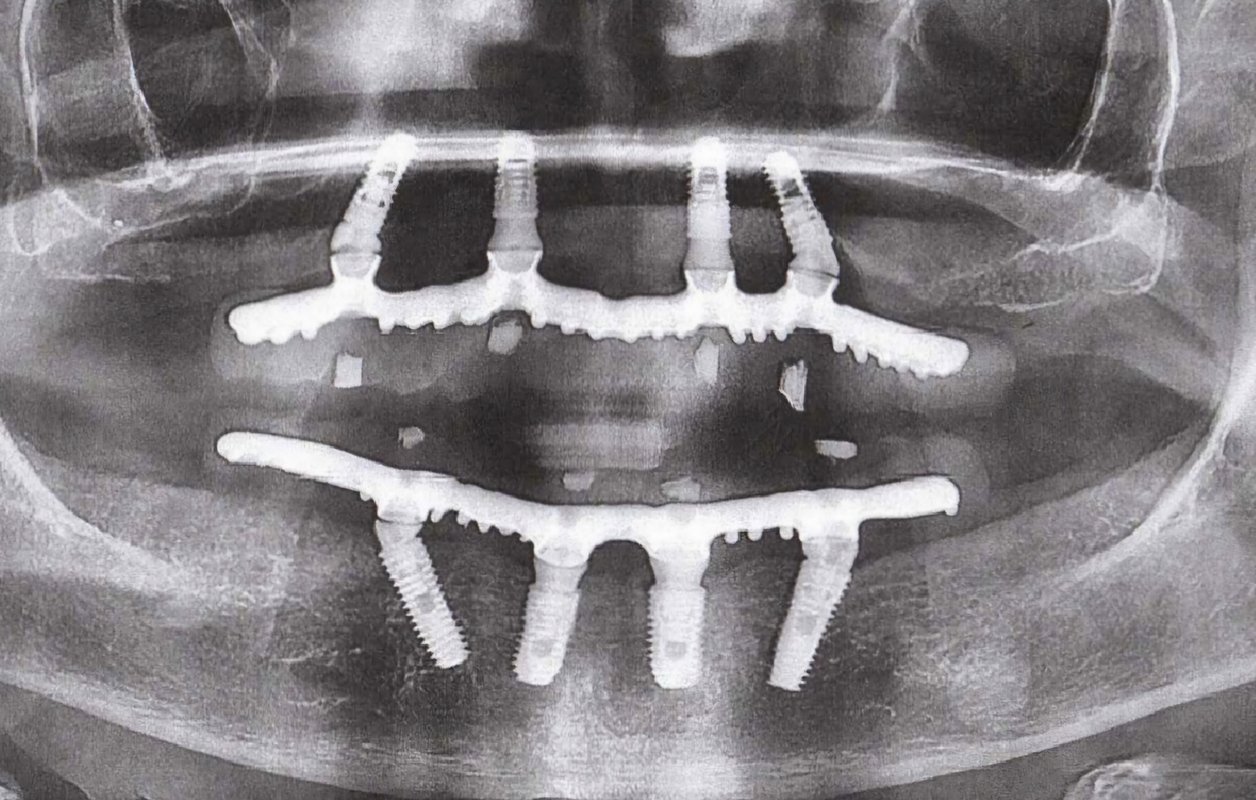

Фотогалерея